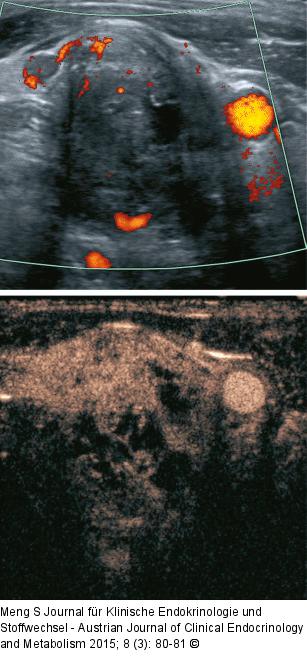

Abbildung 6: Lymphknoten-Ultraschall Ein bereits nativ suspekter Lymphknoten (zervikale Adenokarzinommetastase von der Lunge) zeigt im Power-Doppler kaum ein Gefäßsignal, nach Kontrastmittelapplikation ein heterogenes Enhancement, v.a. mit einzelnen Kontrastmittelaussparungen. |

Ein bereits nativ suspekter Lymphknoten (zervikale Adenokarzinommetastase von der Lunge) zeigt im Power-Doppler kaum ein Gefäßsignal, nach Kontrastmittelapplikation ein heterogenes Enhancement, v.a. mit einzelnen Kontrastmittelaussparungen. |